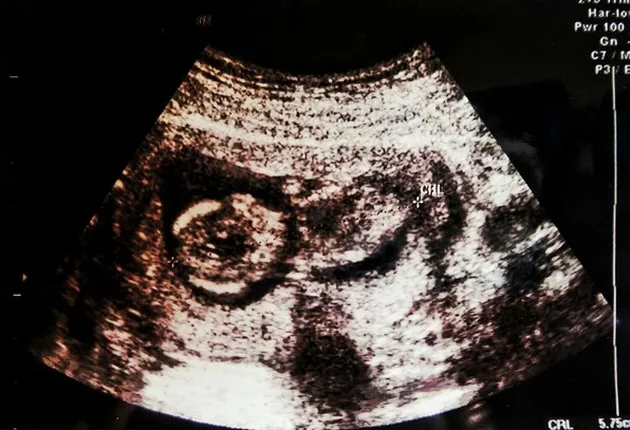

ini nih, foto dari buah hatinya. Pasangan ini juga tak sabar untuk menanti kelahiran anak pertamanya.